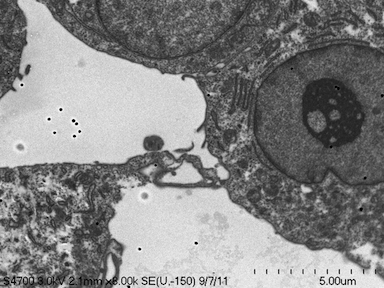

Correlative microscopy is an integration of different microscopy technologies including conventional light, confocal and electron transmission microscopy [6]. Correlative microscopic images usually involve linear or non-linear distortions which are caused by the differences between imaging systems and processing steps. Therefore, the first step of most correlative microscopy based applications is to do registration between two or more microscopic images. An example of correlative microscopic images is presented in Fig. 1.

Refer to caption

(a) Confocal Microscopic Image

(b) Resampling of Boxed Region in Confocal Image

(c) TEM Image

Figure 1: Example of Correlative Microscopy. The goal is to align (b) to (c).